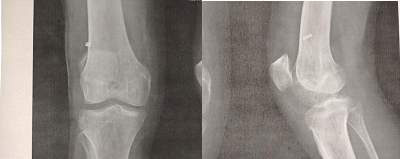

This is a retrospective study that involved 40 patients whose average age was 35 years (with extremes of 18 to 45 years) with a male predominance of 90%. The initial trauma was a sport accident in 70% of cases, a road accident in 20% and a work accident in 10%. The mechanism of injury frequently encountered was a flexion external rotation valgus in 40.7% of cases. The left knee was still the most affected (60%). Subjective and objective laxity was present for all patients with a positive Lachmann and anterior drawer test for all patients MRI showed total interstitial ACL rupture in all patients, associated with meniscal lesions for 10 patients, he femoral fixation (fig 01) was made by an endobutton, in the tibial the fixation was ensured by an absorbable interference screw. The mean overall preoperative score according to Lysholm fell from 66.5 to 87 postoperatively. With an average follow-up of 24 months, the overall results were evaluated according to the IKDC score, they were excellent and good in 87% of cases. with a satisfactory reduction in pain and a resumption of usual sports activity 9 months after surgery. 40% of our sports patients have recovered to a level similar to that before the trauma. No immediate postoperative complications were noted to our patients.

Figure 1: Endobotton Emplacement